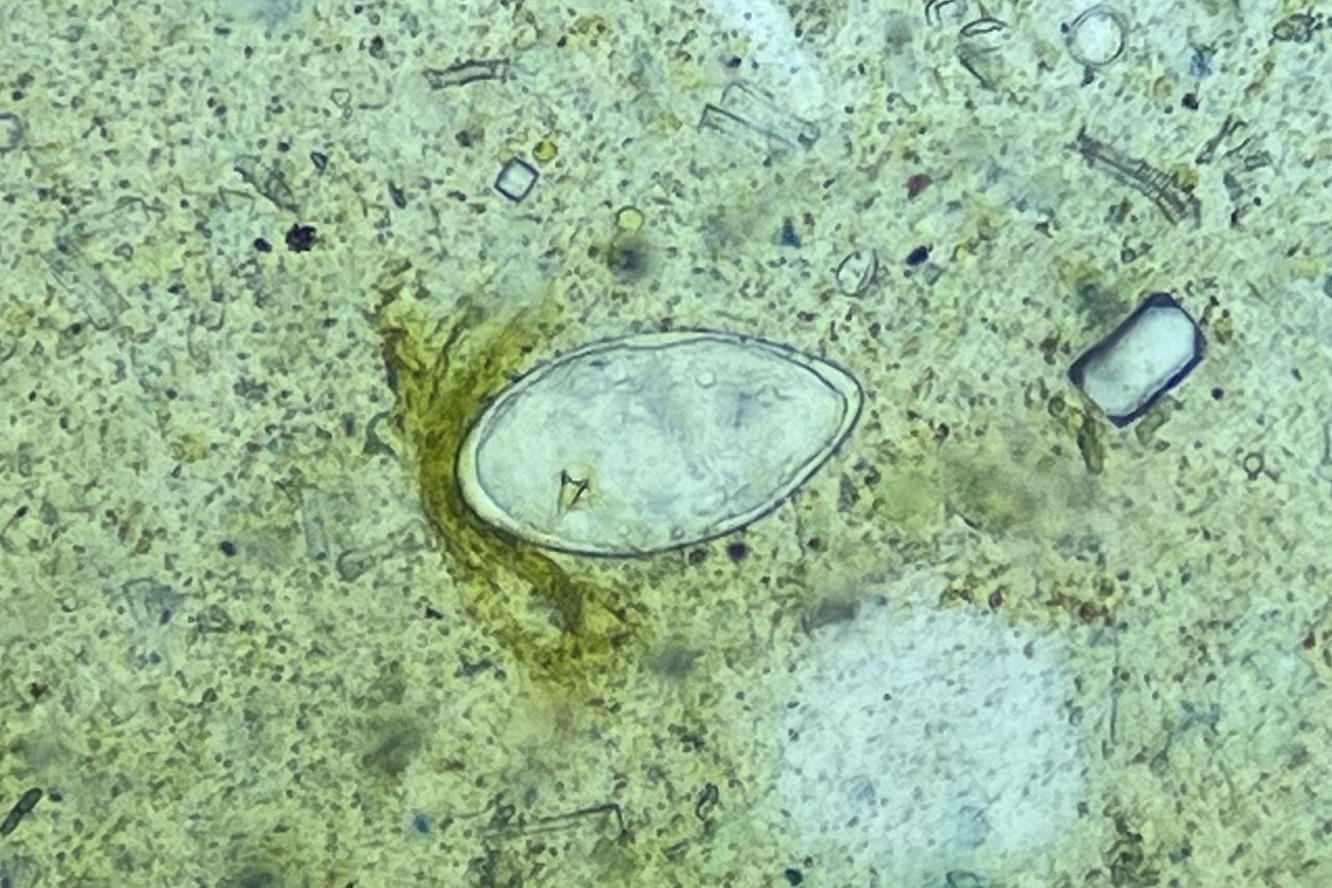

현장 실험실에서는 우리 협회 전문가와 카메룬 보건요원이 함께 검경 작업을 진행하며

전체 대변 검체 3,275건 중 1,917건(54.8%)의 기생충 감염 여부를 분석했어요.

현지 보건인력의 실무 역량을 함께 키워가는 값진 시간이었습니다!

또한 이 조사는 단순한 현장 점검을 넘어,중앙주 전반의 감염 현황을

보건지구 단위로 정밀하게 파악했다는 점에서 중요한 성과를 남겼습니다.

조사 결과, 일부 보건지구에서는

주혈흡충(SCH)과 토양매개성 기생충(STH) 감염이 여전히 높은 수준으로 확인되었으며,

향후 집중 관리가 필요한 고위험 지역을 명확히 식별할 수 있었습니다.